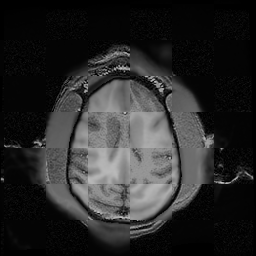

For each of the 10 subjects, we show checkerboard slices in each direction (1) before registration, first row; (2) after rigid->scaleversor->affine registration, second row; and (3) after BSpline registration, third row.

Issac

Issac is a good example of BSpline registration failure.

Ron noted, the reason might be that Issac had his mouth open, unlike most of the subjects registered successfully.